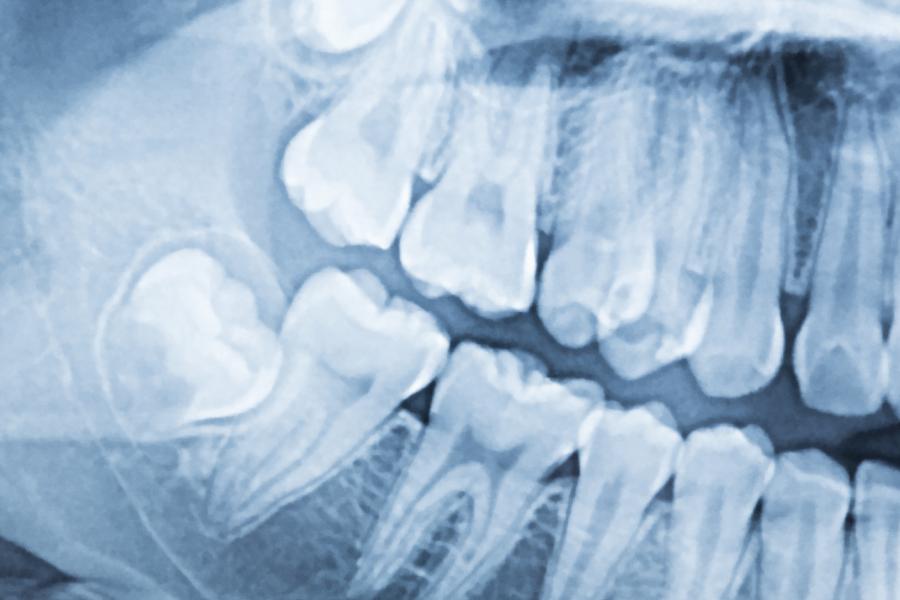

Ósemki mogą przeszkadzać w leczeniu wady zgryzu, uniemożliwiając uzyskanie oczekiwanego efektu. Mowa o sytuacji, w której wpływają na funkcjonalność zgryzu, przez co powodują stłoczenia. Bywa też tak, że ósemka naciska na sąsiadujący ząb, co może prowadzić do uszkodzenia jego korzenia. Kłopotliwa jest także sytuacja, w której ósemka jest zatrzymana (np. wychodzi po kątem lub w ogóle się nie wyrzyna). Taki ząb bywa powodem stanu zapalnego, może prowadzić do rozwoju torbieli lub powodować przesuwanie zębów w łuku.

Zdjęcie rentgenowskie (RTG) z zatrzymanymi ósemkami